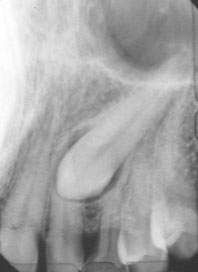

Modalité de localisation : les dents de référence, à savoir les prémolaires et les incisives, lorsqu’elles sont situées dans l’épaisseur de coupe sont représentées nettes et de taille normale. Une inclusion en position vestibulaire sera floue et rétrécie, et en position totalement ou partiellement palatine elle apparaîtra floue et partiellement agrandie (Fig 1, 2).

Rétro-alvéolaires :

C’est un cliché qui représente une image de superposition de plan. Ce genre d’image donne une représentation de la dent dans deux plans de l’espace, du haut en bas et de gauche à droite. Pour situer la dent dans le sens transversal il est nécessaire de prendre un second film. Deux incidences sont nécessaires : orthoradiale et excentrique.

Modalité de localisation :

- Déplacement horizontal du tube ou règle d’Ewan et Clark : deux films sont pris au même endroit, l’un avec une incidence orthoradiale et l’autre avec un rayon principal excentrique (fig 4, 6). Si l’image se déplace dans la même direction que le cône, la dent est située du côté palatin et du côté vestibulaire si l’image se déplace du côté opposé du cône.

- Déplacement vertical du tube : le même raisonnement que pour le déplacement horizontal peut être adopté. Cette fois-ci l’angulation du cône est modifiée dans le sens vertical. Là aussi, l’objet situé du côté vestibulaire se déplacera du côté opposé à la source du rayonnement. S’il est palatin, il se déplacera dans le même sens (Fig 5).

| Fig 6 : Rétro-alvéolaires d’une canine incluse. Sa position palatine est confirmée par le déplacement de la dent dans le sens de la source radiologique (Service d’ODF). |